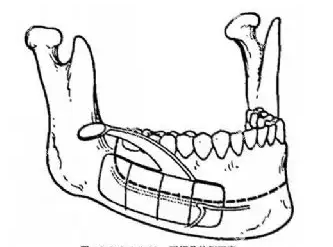

3.骨折与骨愈合问题

颌面骨骼操作不当可能引发骨折,术后固定不到位或功能锻炼不足可能导致骨不连或骨坏死,影响手术成效。